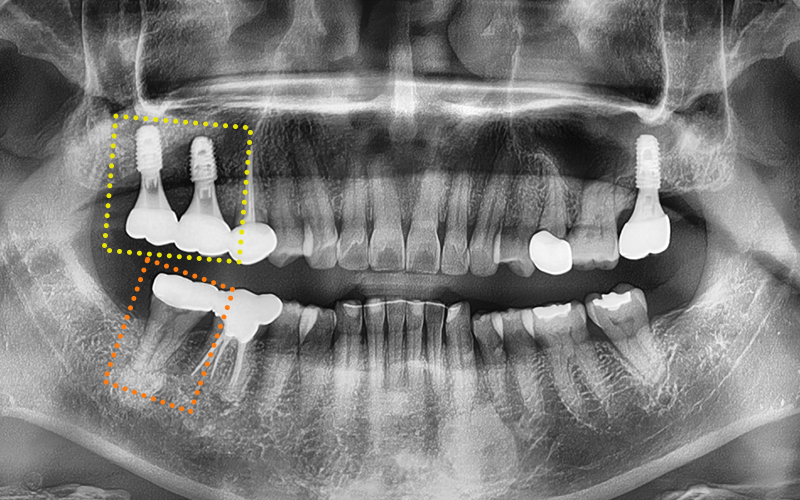

✅ 치료 완료 후 보철물까지 완성!

교합을 섬세하게 고려하여

정밀하게 보철작업까지

완료된 모습입니다!

✅ 전 > 후

2024.11.22

▼ ▼ ▼

2025.04.15

이렇게 성공적인 임플란트 치료사례에 대해

소개해드렸는데요!

환자분께서도 결과에 매우 만족하셨답니다 :)